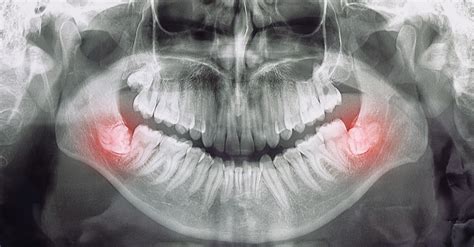

Diente retenido o impactado

Ocurre cuando un diente no puede emerger completamente porque encuentra un obstáculo o falta de espacio. Las muelas del juicio y los colmillos (caninos) son los más propensos a quedar retenidos bajo la encía. Un diente impactado permanece atrapado en el hueso o la encía, a veces mostrando solo una parte visible. Esto suele deberse a falta de espacio (apiñamiento dental), a que la mandíbula es pequeña o a que el diente está mal posicionado.